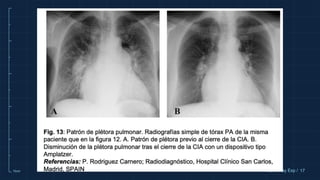

PATRÓN DE PLETORA

PULMONAR

Indica un aumento del flujo en la circulación

pulmonar lo que provoca dilatación de los vasos

pulmonares centrales y periféricos de manera

bilateral y simétrica, frecuentemente

acompañada de cardiomegalia a expensas del

corazón derecho.